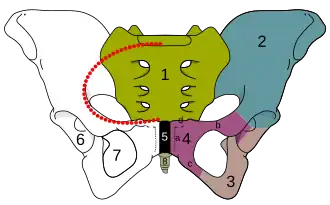

la ligne rouge pointillée correspond à la ligne innominée.

Le foramen obturé (ou trou ischio-pubien ou trou obturateur ou orifice ischio-pubien ou foramen de Bartholin) est un large orifice perforant l'os coxal.

Le foramen obturé est situé dans la partie inférieure de l'os coxal. Il a une forme ovalaire chez l'homme et triangulaire chez la femme[1],[2].

Il est limité en haut par l'acétabulum, en avant par le pubis, en bas par la branche ischio-pubienne et en arrière par l'ischium.